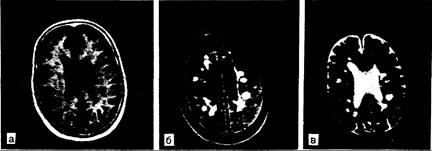

Рис. 341-2. Рассеянный склероз, диагностированный при ЯМР-томографии. В белом веществе видны множественные очаги патологически удлиненного времени релаксации Т1 и Т2. При Т1 (а) бляшки имеют пониженную плотность. При Т2 (б и в) в бляшках обнаруживают усиление интенсивности сигнала. Атрофия мозга умеренной степени выраженности наиболее заметна на рис. в, где самый яркий сигнал дает спинномозговая жидкость. Хотя частота, локализация и распределение таких изменений у большого числа больных с рассеянным склерозом позволяет считать, что эти очаги патологической релаксации соответствуют бляшкам, имеющихся патологоанатомических подтверждений недостаточно. а — исследование по восстановлению инверсии (IR) : TR (время повторения) — 1500, Т1 (время инверсии) — 450, ТЕ (время эха) — 20; б — исследование по спин-эху (SE):TR=2000, ТЕ=60; в — как и в случае б, но ТЕ=120.

Рис. 341-3. Окклюзия правой внутренней сонной артерии, приведшая к развитию инфаркта в правой теменно-височной области.

При исследовании с восстановлением инверсии (IR) со временем релаксации Т1, временем повторения 1500 мс и временем инверсии 450 мс (а) выявляются области удлинения Т1 (темные) в зонах инфаркта; видны также малые участки с увеличенным временем релаксации в заднефронтальных теменных и височных областях лучистого венца с двух сторон. При времени релаксации Т2 (б и в) обнаруживаются измененные зоны, также характеризующиеся удлиненными показателями Т2 (яркие сигналы); более позднее эхо (ТЕ"" 120 мс) обнаруживает некоторую гетерогенность сигнала, но он имеет неопределенный характер, тогда как области более длительных Т2 (самые яркие зоны) соответствуют инфаркту или отеку. (Последовательности спинового эха: TR=2000, ТЕ=60 в случае б и 120 в случаев.)

Рис. 341-4. Артериовенозная мальформация (АВМ).

Тромбоз АВМ с вовлечением правой задней субталамической и верхней мезэнцефалической областей. Темные зоны внутри АВМ при исследовании IR, вероятно, представляют собой очаги патологических изменений в мозге и скорее характеризуются удлинением Т1, чем дефектом заполнения («flow void» effects), в сравнении с бассейном средних мозговых артерий. Яркие зоны при исследовании IR характеризуются укорочением Т1 и удлинением показателей Т2; такое сочетание наблюдается при подострых или хронических кровоизлияниях, некоторых жировых поражениях и метастазах меланомы (вверху: исследование IR — TR= 1500, ТЕ=45; внизу: исследование SE — TR=2000, ТЕ=60).